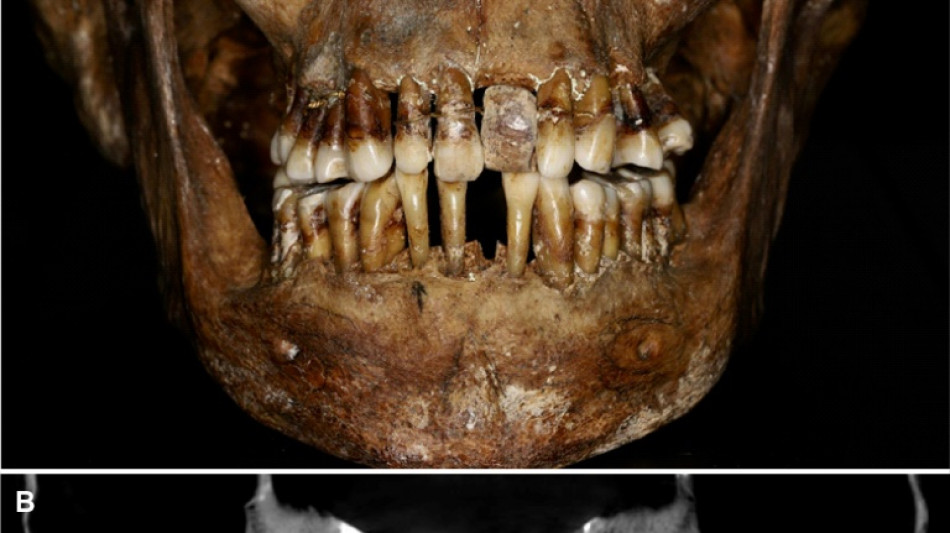

La dentition d'une aristocrate du XVIIe siècle comme marqueur social / Photo: Handout - INRAP/AFP

La sépulture d'Anne d'Alègre, morte en 1619 à l'âge de 54 ans, avait été déterrée lors d'une fouille au château de Laval, en 1988. Embaumé dans un cercueil de plomb, le squelette était particulièrement bien conservé, sa dentition aussi.

Plus de trente ans après, une équipe comprenant des archéologues et des dentistes dévoile qu'Anne d'Alègre était atteinte d'une maladie parodontale qui provoque le déchaussement progressif des dents, selon une étude parue cette semaine dans Journal of Archeological Science.

Les images radiologiques par "Cone Beam", un scanner en 3D, montrent que la patiente portait une prothèse dentaire remplaçant une incisive, soutenue par des fils d'or, ainsi qu'une ligature de contention sur des pré-molaires.

Des examens en macroscopie ont déterminé que cette prothèse était en ivoire d'éléphant, écartant la piste de l'ivoire de dents d'hippopotame, également utilisé à l'époque.

Ce traitement n'a fait "qu'aggraver la situation" de la patiente, explique à l'AFP Rozenn Colleter de l'Inrap (Institut national des recherches archéologiques préventives), auteure principale de l'étude.

A long terme, ce traitement, ainsi que les "multiples resserrages nécessaires, ont entraîné l'instabilité des dents voisines", détaille l'Inrap.